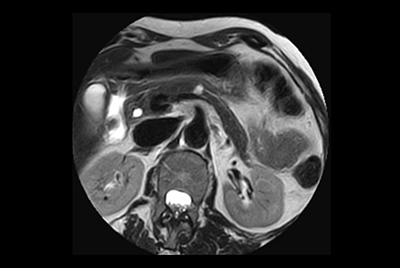

Liver and Pancreas